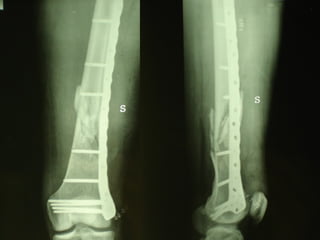

Dal Gennaio 2000 al Febbraio 2006 abbiamo trattato 167 fratture chiuse  con placca percutanea  in 164 pazienti :  27 lesioni diafisarie di gamba, 12 piloni tibiali ,  11 fratture prossimali di tibia, 36 fratture sovracondiloidee di femore, 17 fratture diafisarie di femore, 43 fratture metaepifisarie prossimali di omero, 21 diafisarie d’omero.  156 guarigioni 8 fallimenti

Dal Giugno 2002 al Dicembre 2004 abbiamo trattato 5 fratture esposte: 3 di tibia e 2 di ulna 5 guarigioni

I buoni risultati ottenuti dipendono da 5 punti fondamentali:   una accurata riduzione percutanea della frattura  precise vie di accesso  l’utilizzo della placca che consenta il più lungo braccio di leva possibile il pretensionamento della placca  una sintesi con un ridotto numero di viti

Placche lunghe e pretensionate

Placche lunghe e pretensionate Sintesi con un ridotto numero di viti

Fratture  esposte